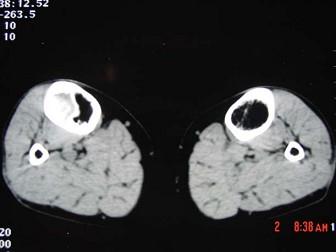

问题 患者 女,19岁,3个月前自觉右胫骨部疼痛,有轻度肿胀,请结合所提供的图像,选择最佳选項 ( )

选项 A、纤维性骨皮质缺损 B、骨样骨瘤 C、造釉细胞瘤 D、骨纤维结构不良 E、骨囊肿

答案 D